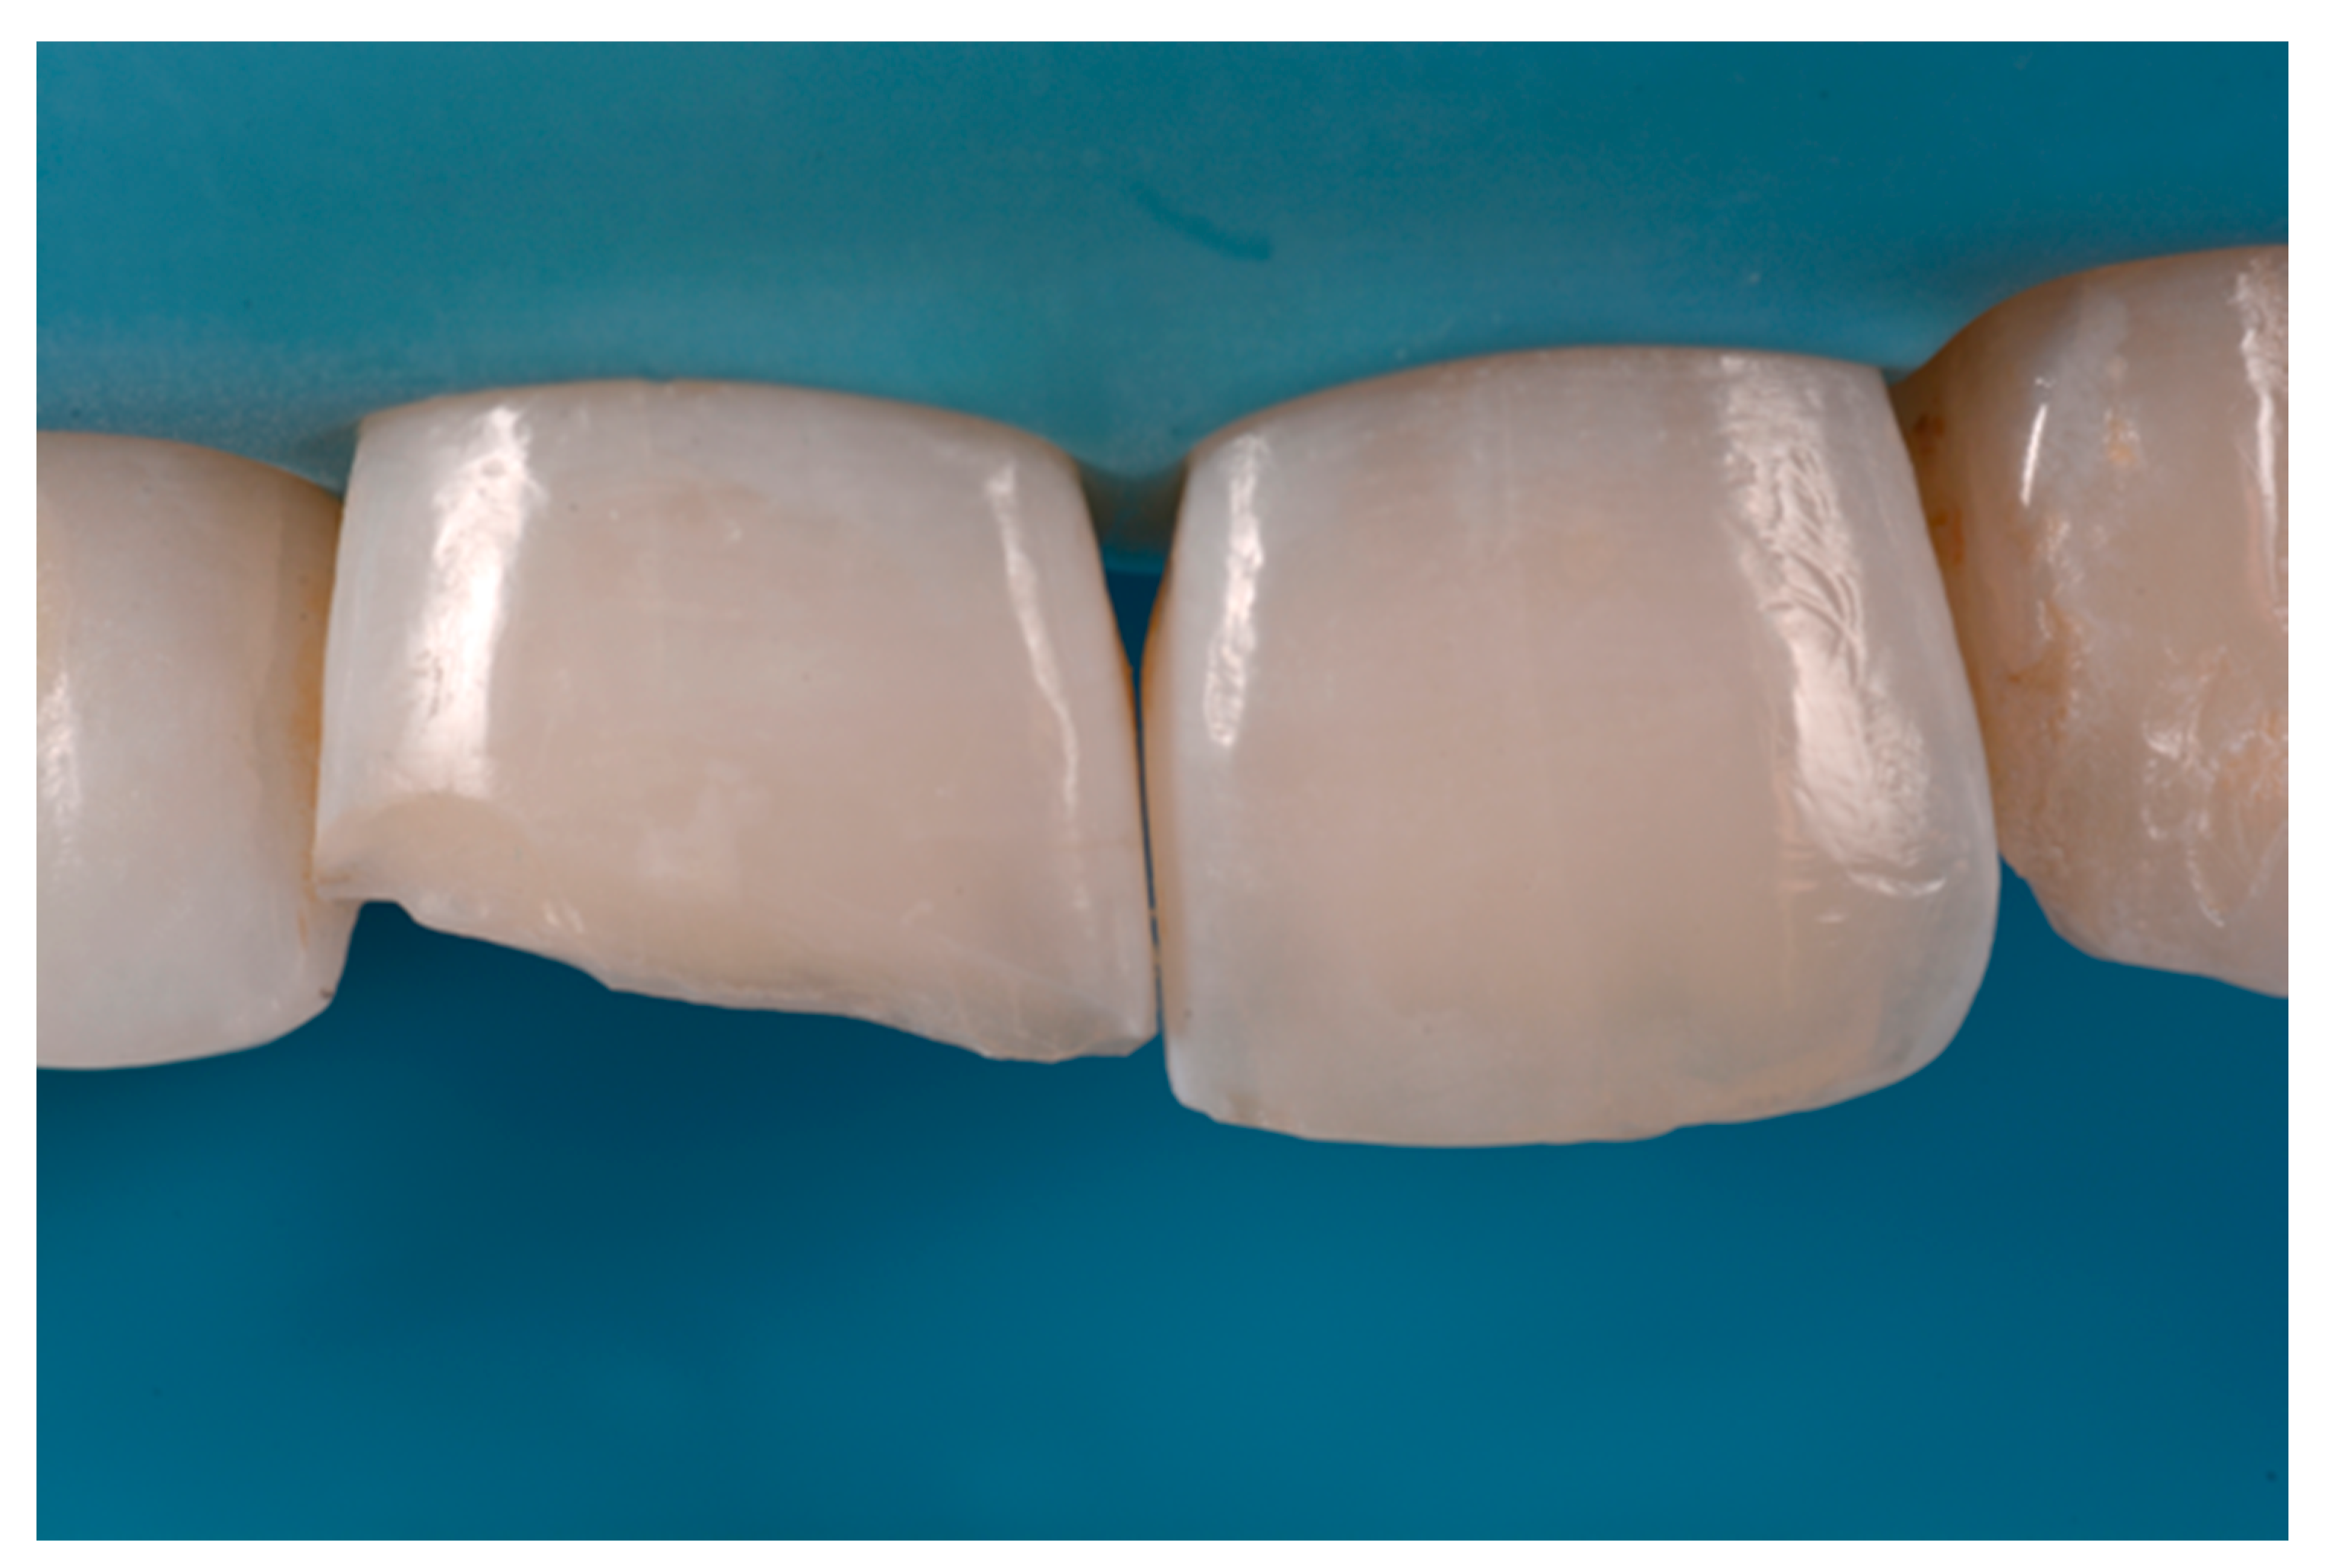

A 42-year old woman presented to the clinic with esthetic concerns related to her upper left lateral incisor (Figure 20). Pre-operative x-rays showed periapical lesion that required retreatment. After retreatment (Figure 21) a treatment plan was proposed to the patient. The ideal treatment would have involved an orthodontic therapy to gain back lost space in mesial portion. The patient decided not to consider an orthodontic treatment and accepted just the restorative proposal (Class IV restoration). Considered the sufficient amount of ferrule no post was applied [16]. Shade was selected as described in previous case, using the button-try technique [14]. After isolation with rubber dam, preparation (Figure 22) and adhesion (Clearfil SE, Kuraray Noritake Dental, Tokyo, Japan), composite frame was completed (Clearfil Majesty ES-2, A1D, Kuraray Noritake Dental, Tokyo, Japan) with silicone index and interproximal transparent mylar matrices (Figure 23). Interproximal walls were considered too thick; therefore, they were reduced (Figure 24) using diamond bur as described in Section 2.1.2. This allowed the internal dentinal body to have the correct volume (Figure 25) and therefore to respect ideal opacity/translucency ratios. Restoration was therefore completed adding enamel layer (Clearfil Majesty ES-2, A1E, Kuraray Noritake Dental, Tokyo, Japan) and performing finishing and polishing procedures (Figure 26 and Figure 27) as described in previous clinical case. The restoration shows good integration 6 months post-operative (Figure 28 and Figure 29).

Figure 22.

After isolation preparation is performed. Reprinted from Restauri diretti nei settori anteriori, G. Paolone, S. Scolavino, © 2021, with permission from Quintessence Publishing Italy.